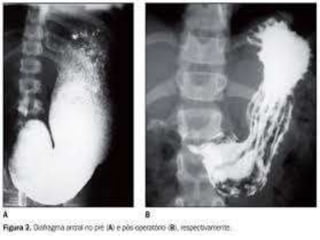

Indicado como meio de contraste radiopaco nos estudos

radiológicos do trato digestório(esôfago, estômago, duodeno,

intestino e cólon);

Uso de contraste: Uso de contraste:

Estudo gastrointestinal Estudo do reto e cólon

Contraste Artificial PositivoBaSO4 Uso de contraste: Uso de contraste: Estudo gastrointestinal Estudo do reto e cólon